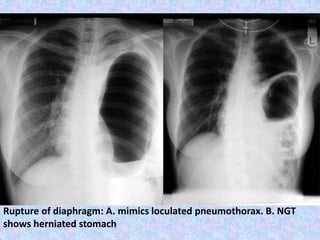

• Diaphragmatic rupture

Rupture of diaphragm: A. mimics loculated pneumothorax. B. NGT

shows herniated stomach